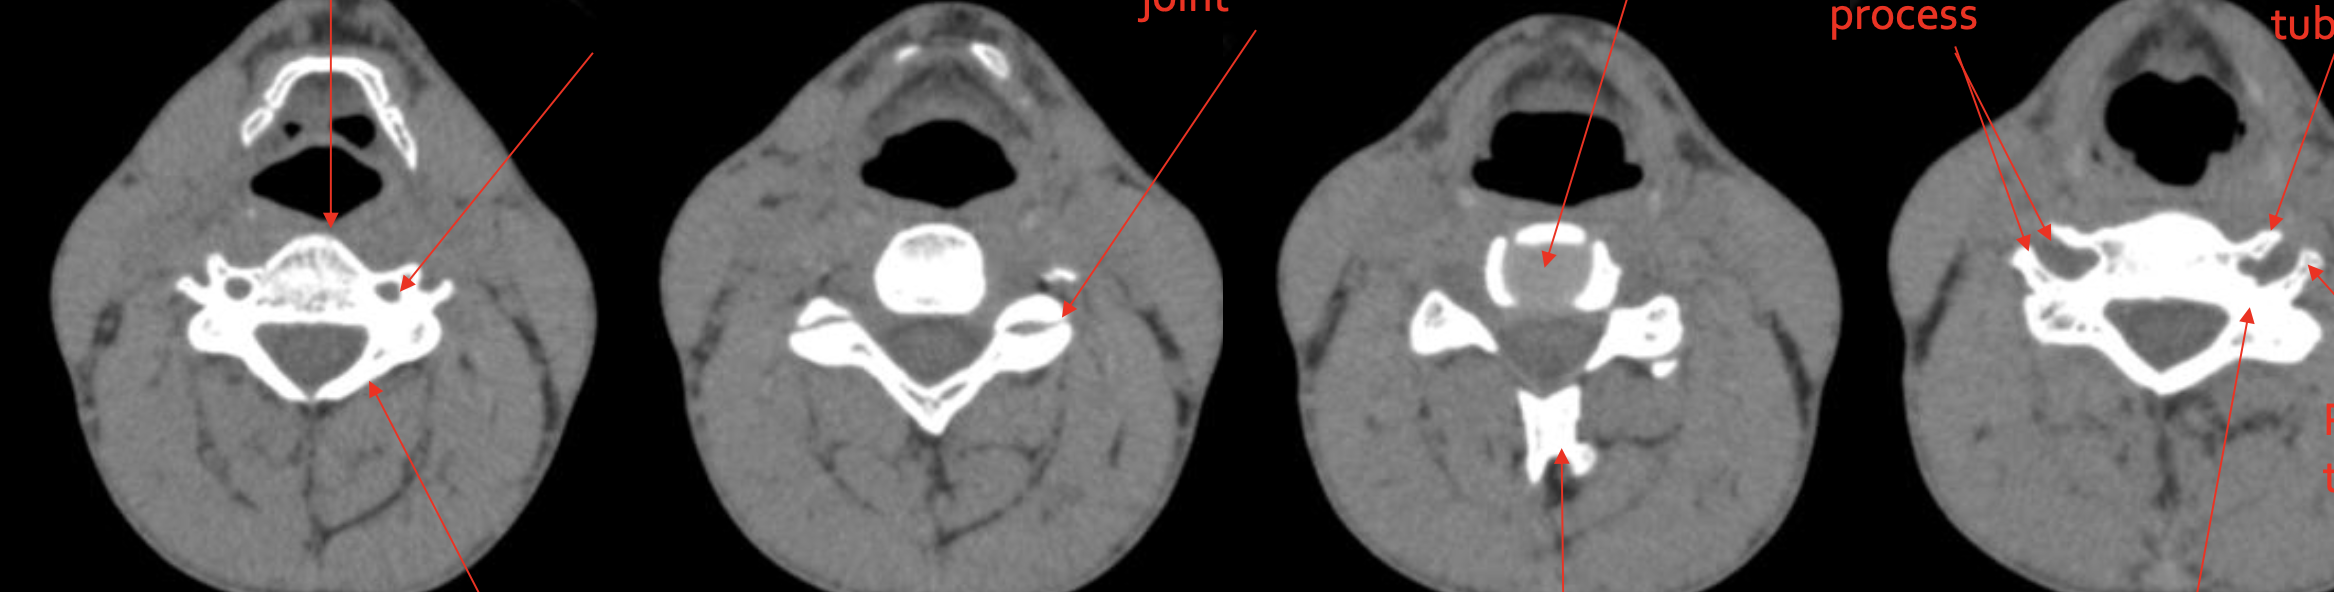

椎体

Vertebral body

椎板

Lamina

关节突关节

Zygapophyseal joint

椎间盘

IVD (Intervertebral Disc)

分叉棘突

Bifid Spinous process

前结节

Anterior tubercle

后结节

Posterior tubercle

椎弓根

Pedicle